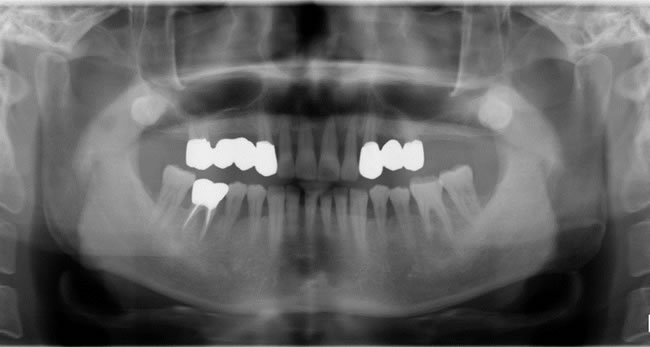

■初診時

9年前、他の医院で歯周病が進行し、上顎の歯はすべて抜歯して、総入れ歯にしないといけないと言われたそうです。血糖コントロールにはよく噛むことが大切ですが、入れ歯はどうしても咀嚼障害がおこり、噛み応えのない糖質の摂食も多くなります。